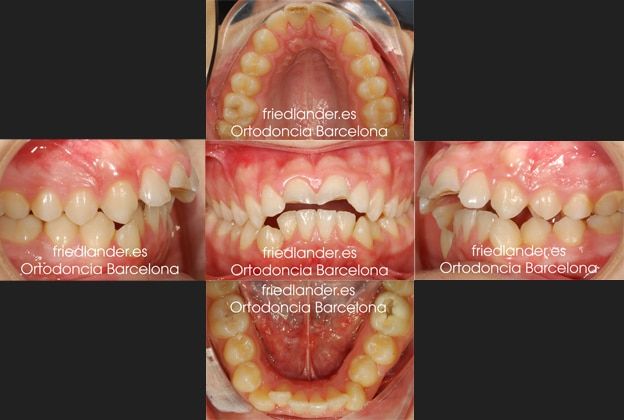

Este caso fue tratado con brackets de autoligado con 4 extracciones. Este paciente de 15 años acude a la consulta por un traumatismo dental en los incisivos superiores.

Debido al resalte que presentaba hay más probabilidad que, en caso de un golpe, se fracturen primero los incisivos centrales. Los incisivos fueron tratados con endodoncias y después con unas reconstrucciones provisionales se restauró la forma original de lo dientes.

Al poco tiempo el paciente volvió con las reconstrucciones rotas por la oclusión tan complicada que presentaba y pidió una solución para su boca.

Al hacer el estudio de ortodoncia se observó una clase II una extrusión de los incisivos inferiores de unos 5-6mm con tendencia a una mordida abierta anterior, apiñamiento inferior moderado y una arcada superior y paladar estrecho. Una gran caries en el primer molar inferior del lado izquierdo.

El tratamiento fue planteado con extracciones para poder cerrar la mordida, mejorar la clase II y solucionar el apiñamiento. El plan de tratamiento consistió en extracciones asimétricas en la mandibular extrayendo el primer premolar inferior en el lado derecho y en el izquierdo extraer el primer molar con la enorme caries que presentaba y la retracción de los dientes con microtornillos. Aunque ortodócicamente hubiera sido más fácil hacer extracciones simétricas, en este caso al tener un diente que requiere una endodoncia decidimos extraer éste y no un diente sano.